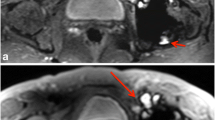

No statistical difference was found between conventional and CS in image quality or occurrence of artifacts. Reader 1 found significantly more motion artifacts than reader 2 for contrast-enhanced 3D T1. This was due to a difference of appreciation of the motion artifact; indeed, reader 1 mentioned even very slight motion observed at the top of the brain whereas reader 2 mentioned only large bulk motion artifacts. There was a marked preference for the conventional sequence for reader 1 whereas reader 2 did not mention such a preference. Indeed, for contrast-enhanced 3D T1, CS exhibited globally less noise in the white matter area and a blurrier transition between the white and gray matter, which is illustrated in Fig. 3. For 3D FLAIR sequence, Fig. 4 illustrates the different features of CS with globally less noise but also less visibility of very small structures. This was however not impairing the ability to detect lesions in the sequence since both readers did not find diagnostic difference in any patient. This was also not confirmed by CNR measurements which were very similar between conventional and CS.

Brain 3D FLAIR sequence, conventional (left) versus CS (right). This example illustrates the different aspects of CS sequence with globally less noise but also less visibility of very small structures (see the cerebellum for example). Note that the white matter lesions in the frontal lobe are well visible on both sequences

Wrist 3D PD SPAIR sequence

The artifacts were (significantly for reader 2, p = 0.037) more present in conventional sequence (mainly motion) with a perfect agreement between readers (κ = 0.82 for conventional and κ = 1 for CS). Both readers often found no preference between sequences or a preference for CS. Diagnostic findings were similar, except in one case for reader 1, for which the conventional sequence had important motion artifacts. The CNR was slightly higher for CS compared with that of the conventional (not significant, p = 0.064).